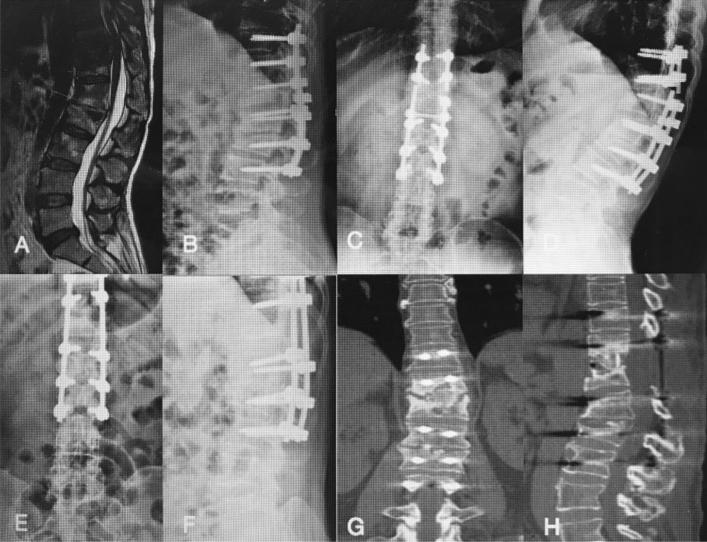

A retrospective study investigated the results of the lamina with spinous process (LSP) as a bone graft in one-level thoracic or lumbar spinal tuberculosis with the one-stage posterior approach of debridement, fusion and internal instrumentation. Data from 35 patients from January 2013 to December 2015 were analysed. Surgery time, blood loss, hospitalization time, drainage volume, and follow-up (FU) duration were recorded. The visual analogue scale (VAS), Oswestry Disability Index (ODI), erythrocyte sedimentation rate (ESR), C-reactive protein (CRP), American Spinal Injury Association (ASIA) grade, segmental angle, and bone fusion were compared between preoperative and final FU. All of the patients were followed up for a mean 43.90 ± 10.39 months. The mean age, surgery time, blood loss, hospitalization time, hospital cost and drainage volume were 33.65 ± 11.06 years, 182.40 ± 23.82 min, 280.80 ± 76.82 mL, 14.05 ± 3.58 days, 74,382.00 ± 11,938.00 yuan, and 340.00 ± 167.20 mL, respectively. VAS and ODI were significantly improved at the final FU. The ESR and CRP recovered to normal. The mean angle of 24.35 ± 5.74°preoperatively showed a significant difference between 1 week, postoperatively and final FU. Although there were the loss of angle at final FU comparing with the 1 week postoperatively, it still maintain the good alignment and the segmental stability. All patients achieved bony fusion with a mean time of 12.90 ± 3.91 months. In conclusion, the LSP as a structural bone graft is reliable, safe and effective for segmental stability reconstruction, which could be one choice for surgical management of thoracic or lumbar spinal TB.